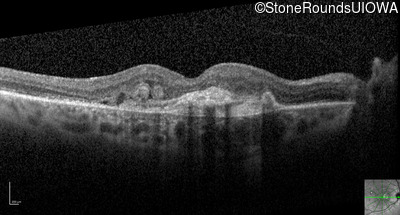

Optical Coherence Tomography - Right - 20/200

Exemplar / OCT Stack

Optical Coherence Tomography - Left - 20/20 -1